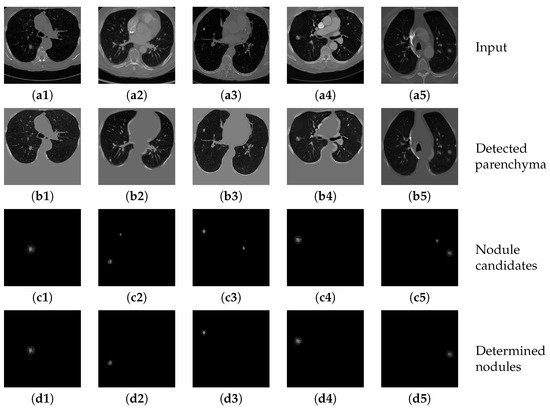

Figure 14(b1–b5) show several example results of the parenchyma segmentation sub-network. Table 5 shows the performance of the proposed parenchyma region segmentation sub-network, including precision, sensitivity, specificity and dice value. The average dice value of the proposed method is 0.8636, and the precision, sensitivity and specificity are 0.8792, 0.8878, and 0.9590, respectively. It can be considered that the proposed method achieves convincing performance on two datasets. The high dice value and sensitivity further prove that the segmented parenchyma mask is very close to the ground truth, which can guarantee the performance of the following nodule candidate detection.

Figure 14(c1–c5) show the results of applying the nodule candidate detection sub-network to the same input images in Figure 14(a1–a5). In addition, Figure 14(d1–d5) show the results of determining “true nodules” from the nodule candidates in Figure 14(c1–c5), respectively. Table 6 shows the performance of the proposed nodule candidate detection sub-network with respect to sensitivity and specificity. The proposed method achieves a quite high rate of sensitivity with an acceptable specificity, which demonstrates that the sub-network can detect most of the true nodules accurately with only a little over-estimation of other tiny tissues that can be further refined by the following nodule determination sub-network.

Figure 14. The results of detecting parenchyma regions, nodule candidates and determining nodules by the proposed cascaded network on five different chest CT images.